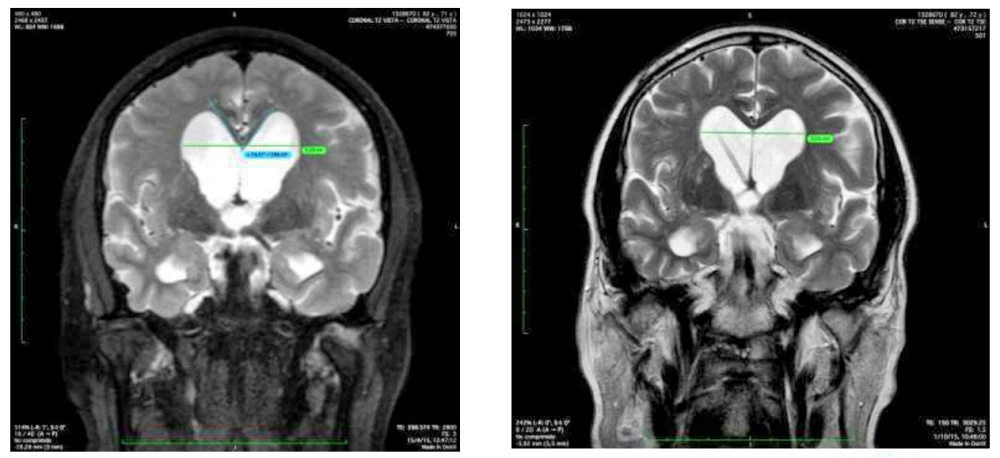

Hallazgos en Resonancia Magnética – Índice de Evans y Ángulo Calloso

La resonancia es realmente una herramienta muy precisa para hacer el diagnóstico:

Edema transependimario: Primero porque se ve el edema transependimario, que se ve como esta zona blanca alrededor de los ventrículos.

Ángulo calloso: Después porque hay unos ángulos que se pueden medir. Este ángulo que es agudo, menor de 90º, es porque el globo ventricular, como esta estructura del cuerpo calloso es muy fija, lo que va a hacer el aumento de presión de los ventrículos es cerrarlo sobre esa estructura.

Índice de Evans: Y después también hay un índice que es la relación entre toda la corteza cerebral de esta longitud y la longitud del ventrículo.

Aparte de eso se puede acabar haciendo estudios muy sofisticados de cómo circula el líquido cefalorraquídeo por el acueducto, de manera que se puede acabar teniendo una clara idea de que estamos ante una hidrocefalia arreabsortiva.